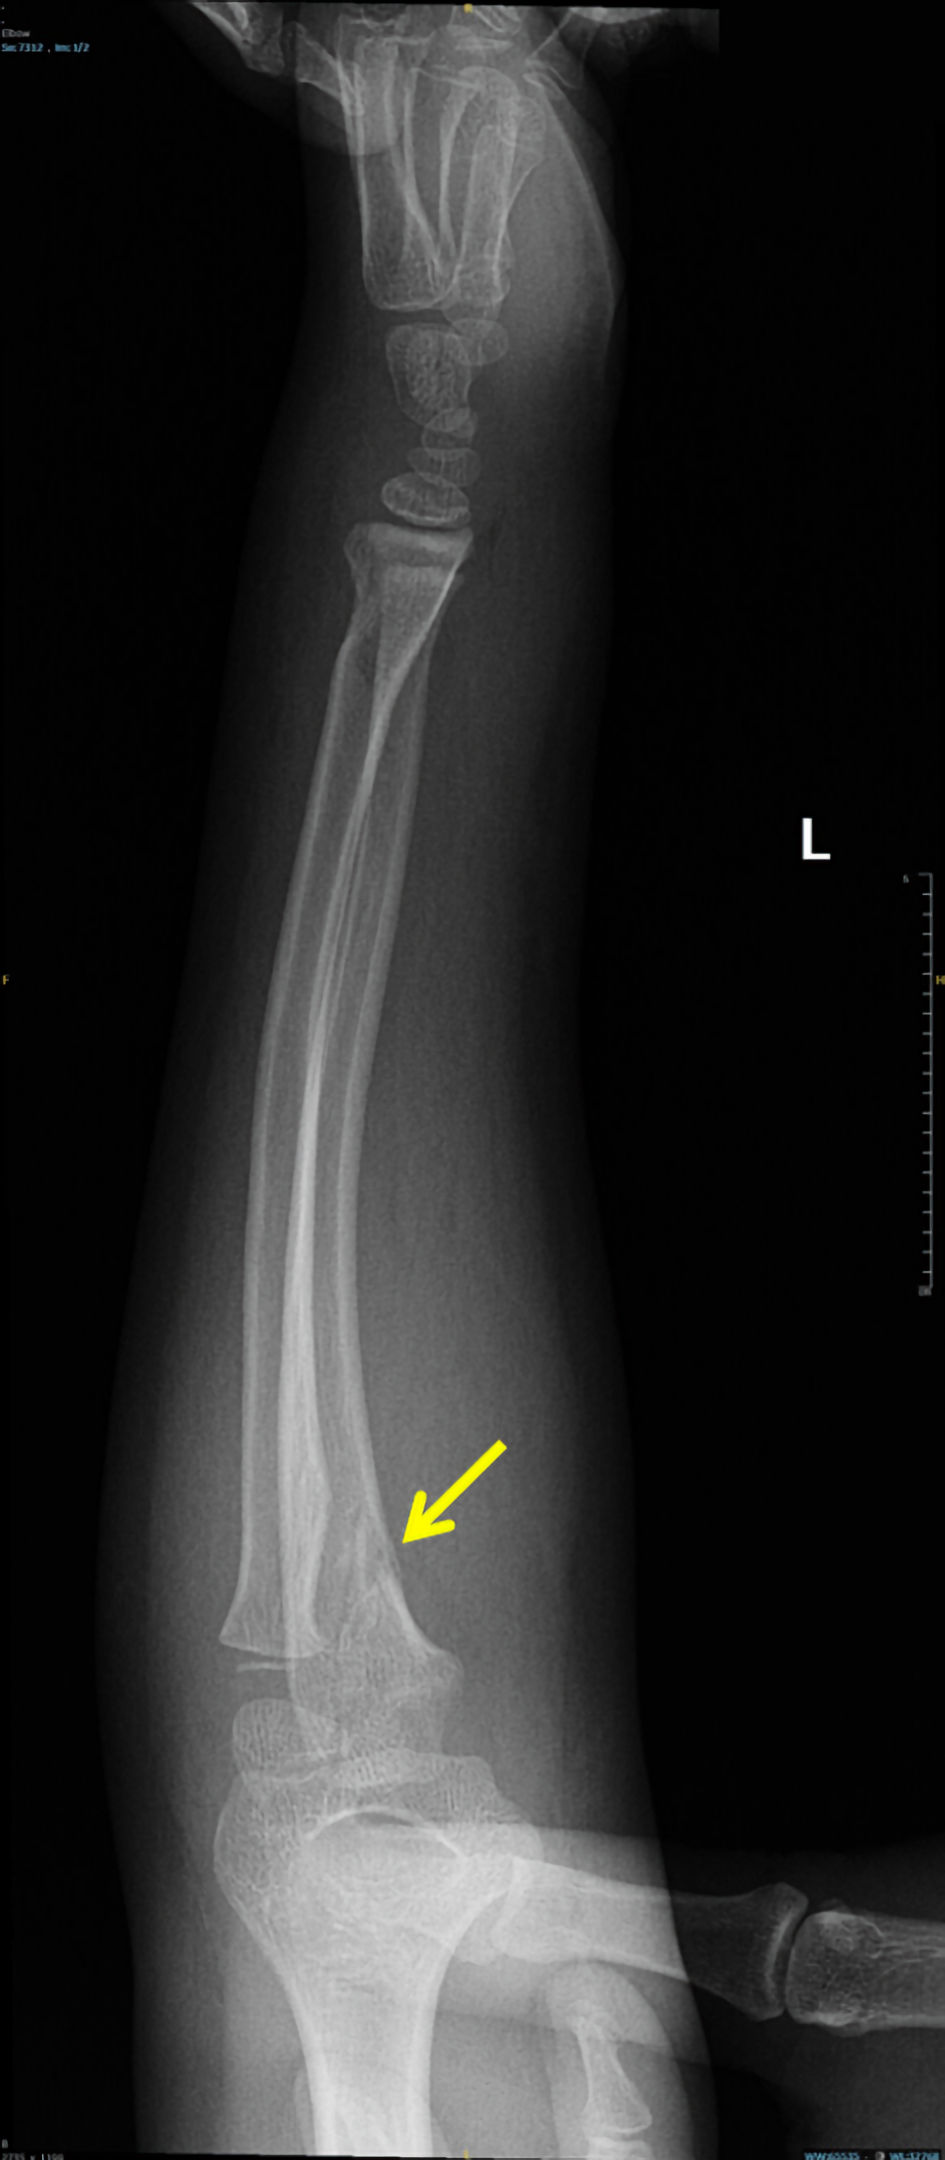

Capillary refill was delayed (3 - 4 s), and the radial pulse was absent on palpation and undetectable by Doppler. However, pulse oximetry readings were obtainable from the left thumb, middle, and ring fingers. She was afebrile and hemodynamically stable except for tachycardia (heart rate 120 beats per minute (bpm)). Urgent radiographs demonstrated non-displaced proximal ulnar and distal radial fractures of the left forearm (Figs. 1, 2).

Click for large image

Figure 2. Anteroposterior forearm radiograph demonstrating proximal ulnar fracture (arrow).